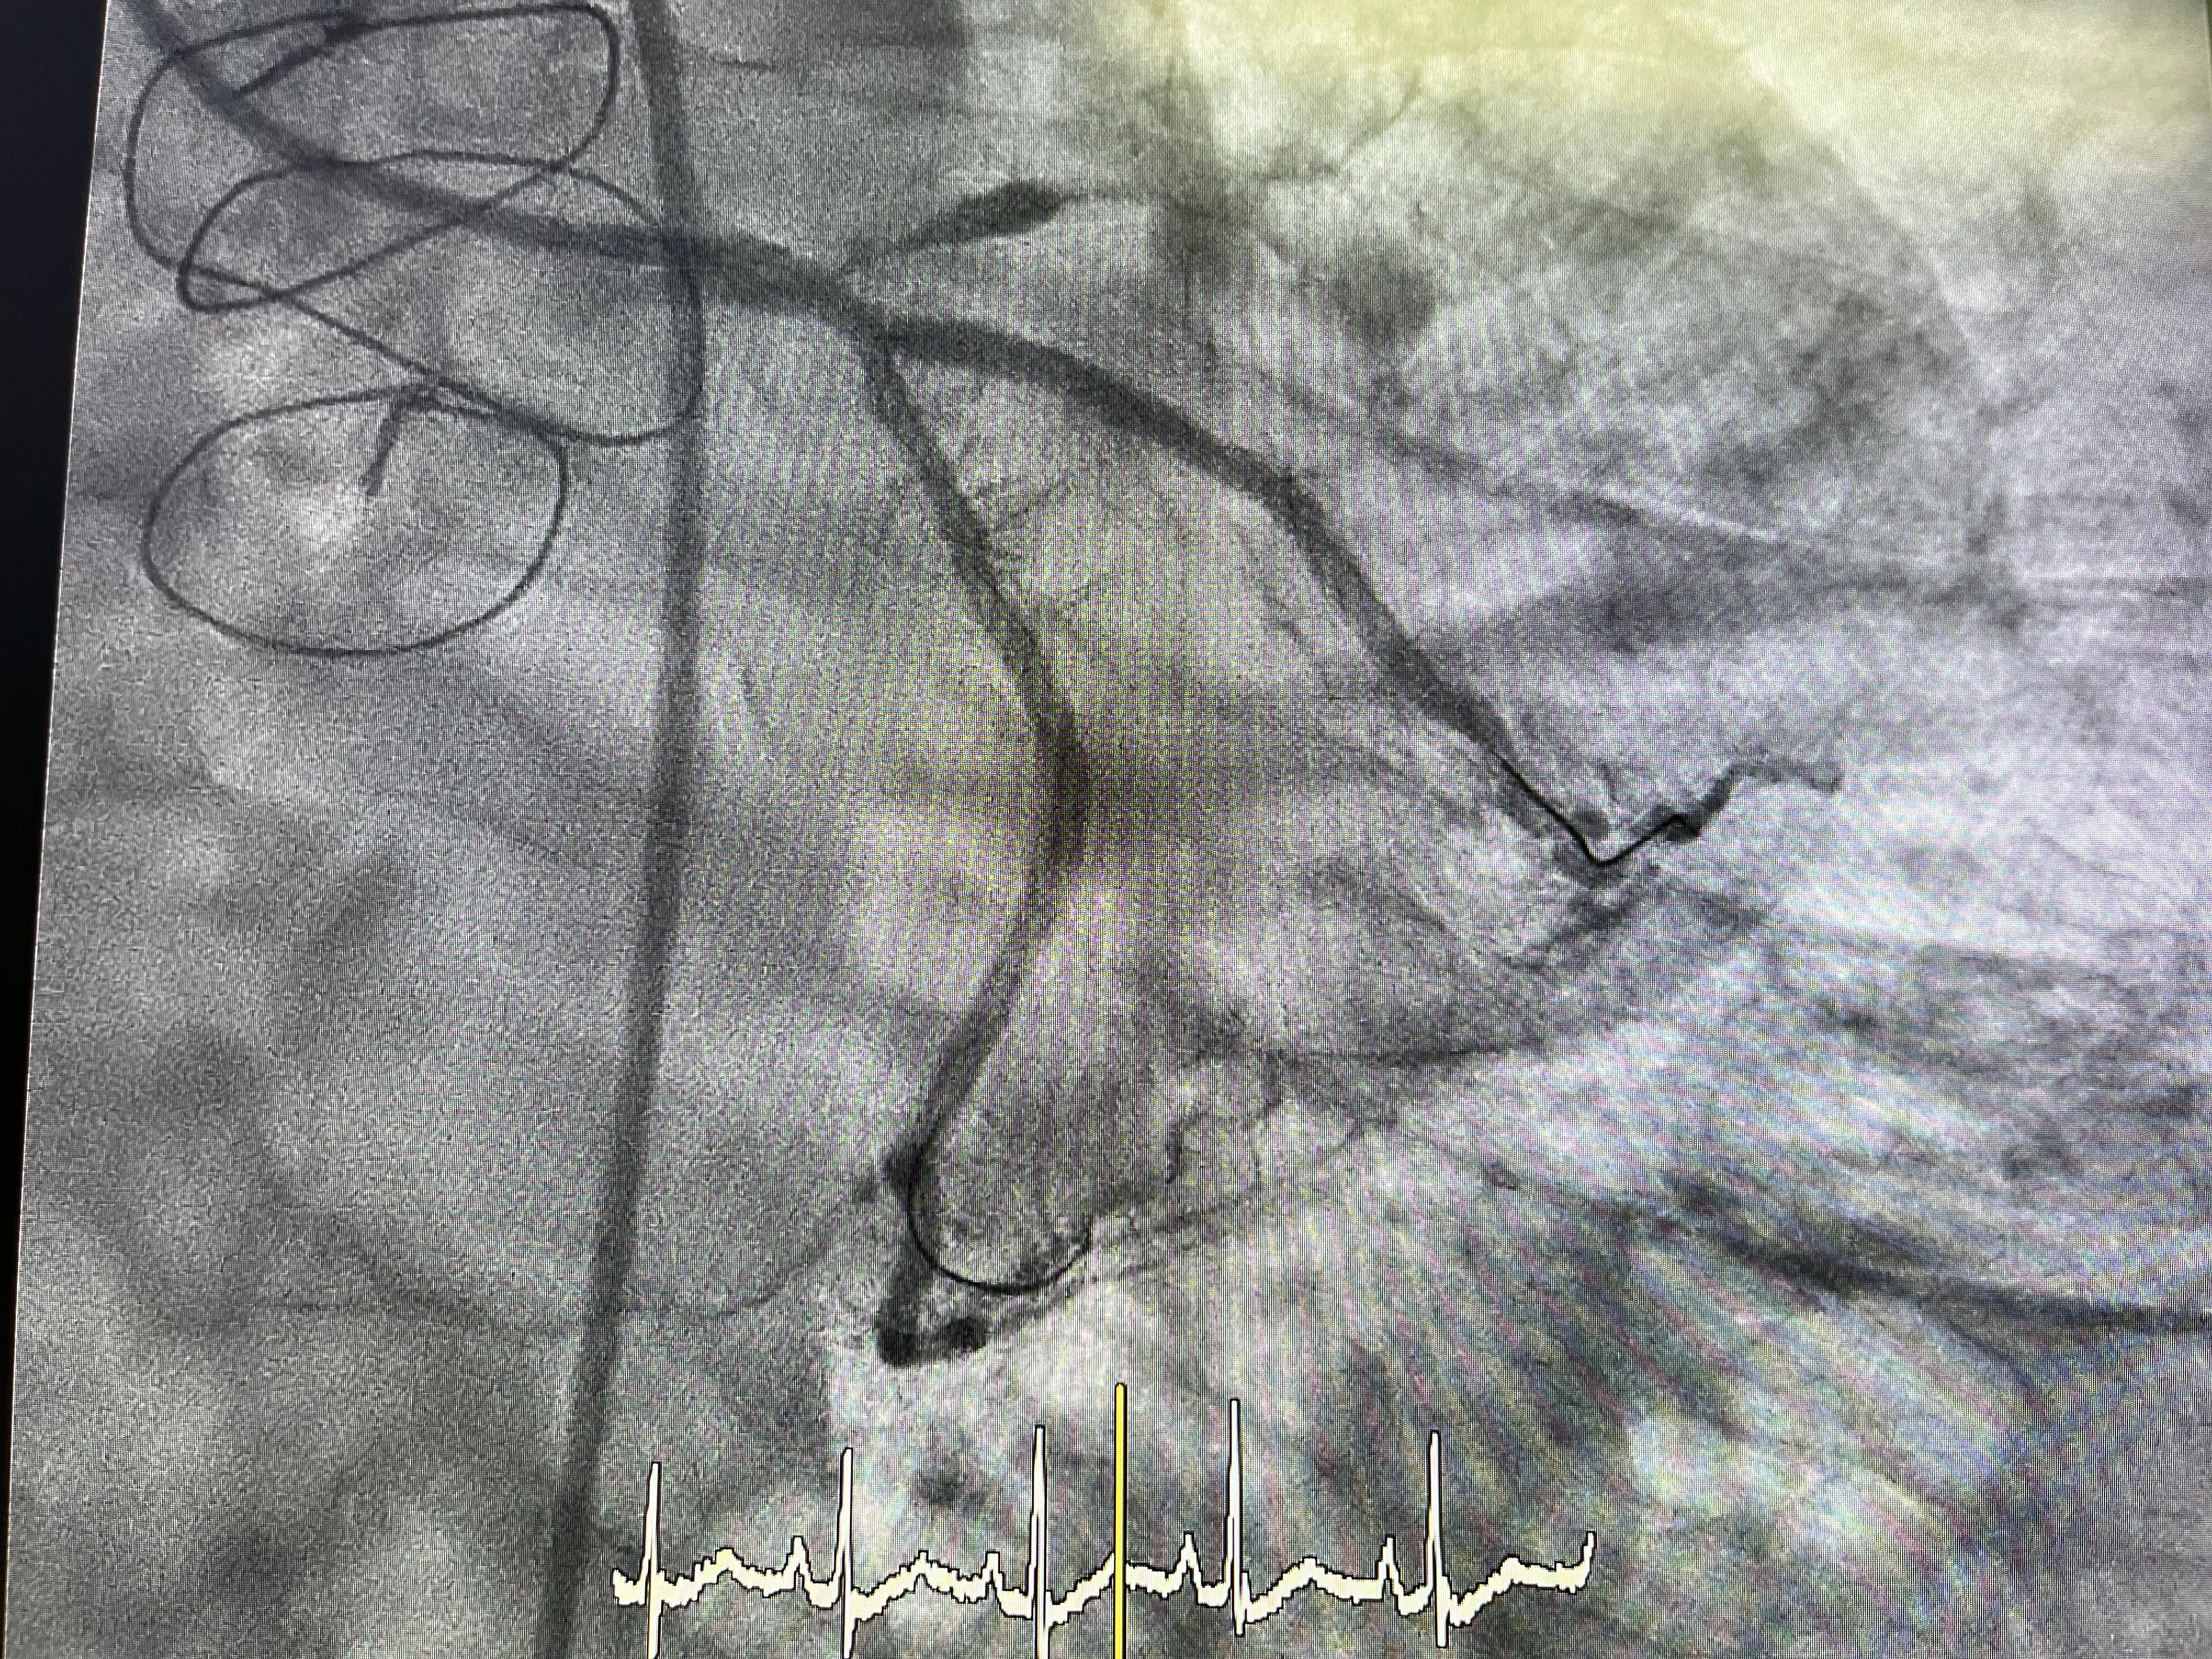

Concepto de irrigación retrógrada de la descendente anterior

En este caso, el bypass está funcionando adecuadamente y proporciona irrigación a la arteria descendente anterior de manera retrógrada. Esto significa que el flujo sanguíneo se dirige hacia atrás desde el bypass hacia la arteria, asegurando que el músculo cardíaco reciba el oxígeno y los nutrientes necesarios para su funcionamiento. Esta irrigación retrógrada es vital para mantener la viabilidad del tejido cardíaco, especialmente cuando la arteria original está obstruida.

Hallazgos en la coronaria izquierda: circunfleja y descendente anterior

En cuanto a la coronaria izquierda, se identificó que el ostium de la arteria circunfleja estaba a punto de obstruirse completamente. Además, la arteria descendente anterior estaba ya completamente bloqueada. Sin embargo, gracias al bypass previamente realizado, la descendente anterior está siendo irrigada adecuadamente, lo que mitiga el impacto de la obstrucción en el flujo sanguíneo al corazón.